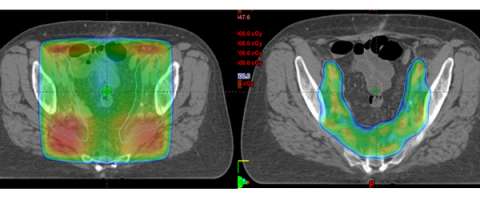

IMRT is a treatment advance that allows us to modulate the intensity of the radiation dose within a given radiation field. This means that the distribution of the radiation dose can be sculpted more finely around targets of interest while sparing more normal tissues. An example of this can be seen below where the axial CT image on the left is an example of a 3D-conformal plan and on the right is an example of an IMRT plan on the same patient. One can see that the IMRT plan allows the majority of the dose to be placed around the lymph nodes (which is the target) while sparing the bowel centrally.